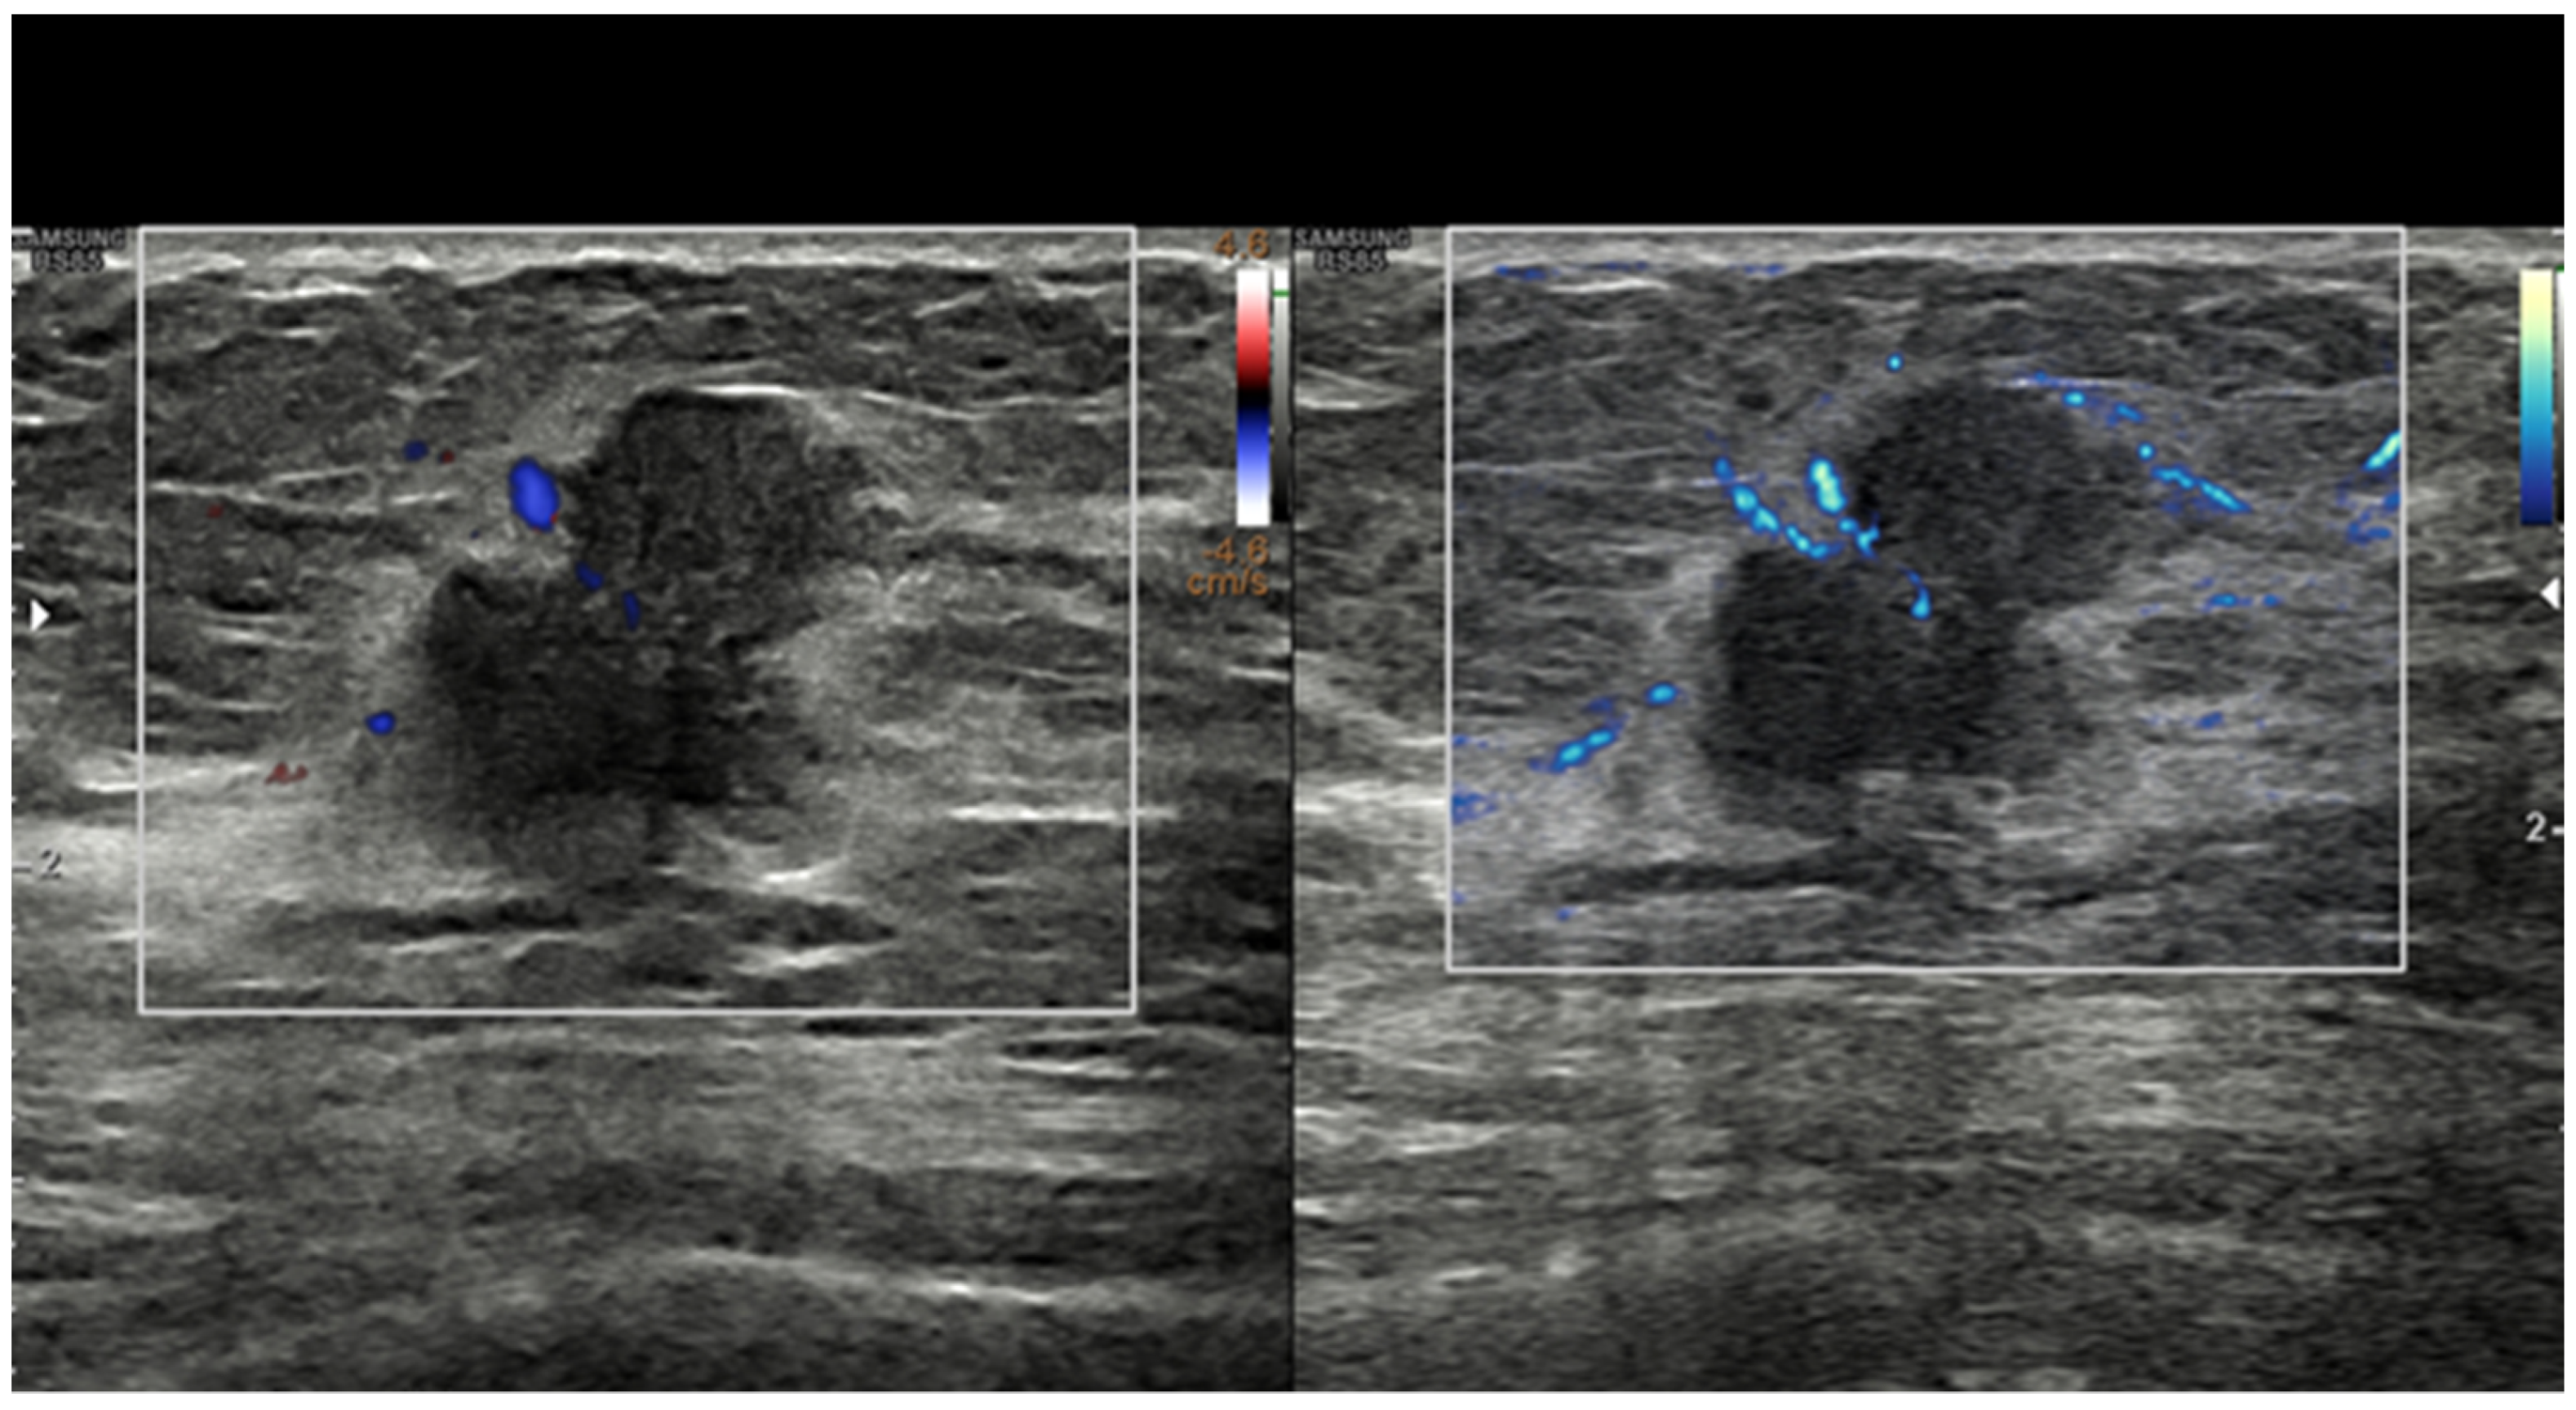

Cancer growth is based on neoangiogenesis, i.e., the tumor-induced development of a vascular network. Detecting these flow signals and assessing their characteristics in terms of number, distribution, and appearance are consequently of paramount importance in tumor characterization and monitorization [12,13,14,15,16,17,18,19,20,21,22,23,24,25,26,27,28]. Even if appropriately set to identify small, low-flow vessels, conventional Doppler techniques, including color Doppler and power Doppler, have a limited sensitivity. In recent years, almost all companies have developed filtered techniques capable of working at a higher frame rate and consequently detecting tiny intra- and peri-tumoral flow signals. With these new software facilities, the background and tissue motion artefacts are suppressed and US sensitivity, spatial resolution, and temporal resolution are significantly improved [29,30,31,32,33,34,35,36,37,38]. Some companies have also developed systems capable of quantifying the number of colored pixels within the box, thus quantifying the flow intensity [39]. If a new microvascular tool is available on the scanner, we encourage users to refrain from still using conventional Doppler modalities for breast imaging and to employ more advanced techniques (Figure 1).

Figure 1. Breast invasive ductal carcinoma. Vascularization as assessed with power Doppler (left) and with MV-Flow (right). Recently developed techniques such as MV-Flow are more sensitive to slow flows and offer a better display of tumor vessels.